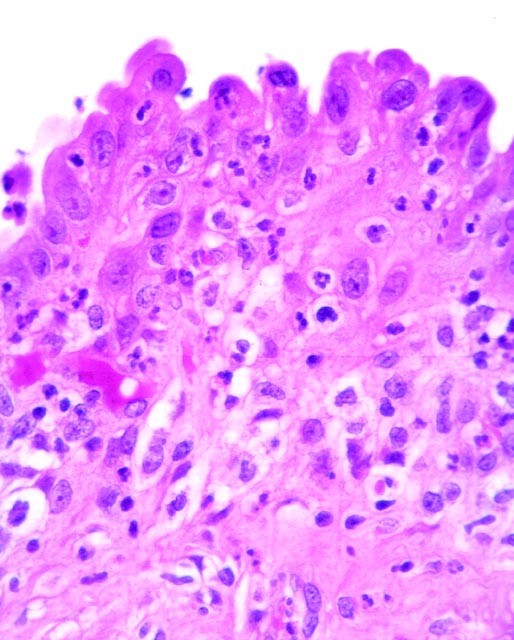

Reactive atypia of the surface biliary epithelium with intraepithelial and subepithelial neutrophils.

FIGURE 7